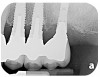

Fig 3. The implants were treated with a Nd:YAG laser. A thrombogenic clot was present at the completion of this treatment.

Figure 3

Fig 4. Clinical view of the area 3 months post-therapy. Shallow probings of 3 mm were present around the dental implants with absence of bleeding. However, the mucogingival deformities remained on the premolar implants and would require treatment.

Figure 4